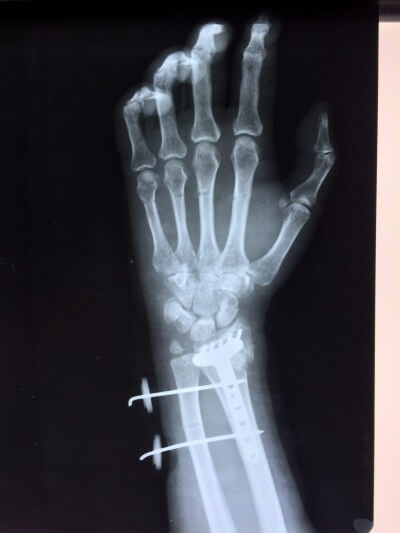

Функциональная и трудовая реабилитация больных с отдаленными последствиями повреждений кистевого сустава

ТРАВМАТОЛОГИЯ

Лечение и реабилитация больных с повреждениями кистевого сустава